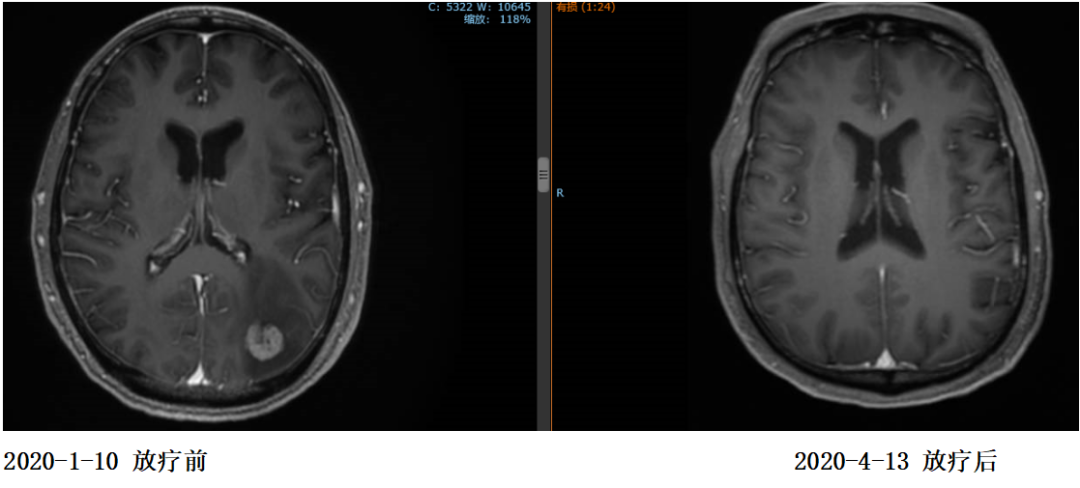

复查:2020.4复查颈部CT及全腹部+盆腔MR大致同前,脑MR示病变较前明显缩小,评估PR。

2020年4月15日开始继续行赫赛汀+希罗达维持治疗。

2020年11月4日复查颈部胸腹盆CT大致同前,脑转移灶明显缩小,继续赫赛汀联合希罗达维持治疗。

这是一例HER2阳性晚期胃腺癌一线应用赫赛汀靶向治疗联合化疗获得较好疗效的成功案例。该患者曾于2017年6月行胃癌根治术,术后予10周期FOLFOX6方案辅助化疗。2018年10月影像学检查并确诊全身多发转移(HER2过表达型,pMMR),并开始予顺铂+氟尿嘧啶联合赫赛汀方案治疗5周期,疗效评估达到PR。2019年2月开始予赫赛汀+希罗达维持治疗。2020年1月确诊枕叶及右侧小脑半球多发转移(肝脏、双肺、颈部淋巴结无进展)。遂开始行左侧枕叶及右侧小脑转移灶放疗。因新冠疫情影响,2020年1月~4月间的赫赛汀治疗中断。2020年4月15日复查示脑转移灶较前明显缩小,继续赫赛汀+希罗达维持治疗。该患者一线治疗PFS达15个月左右。